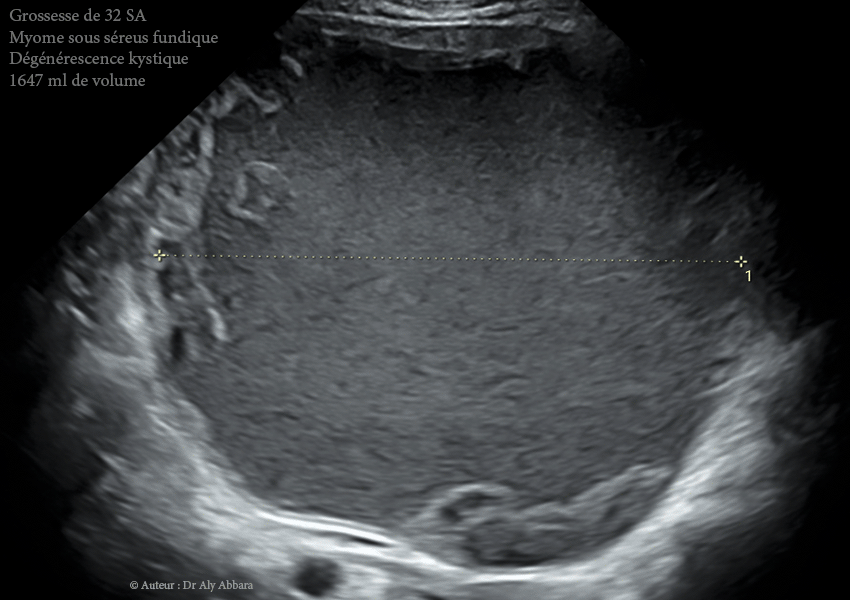

Images échographiques et séquences vidéo montrant une grossesse intra-utérine évolutive de 32 SA survenant au sein d'un utérus porteur d'un myome sous-séreux fundique (classe 7 de la classification FIGO 2011).

• Il s'agit d'un d'un volumineux myome de 120 x 160 x 165 mm de diamètres, soit = 1647 cm3, découvert fortuitement lors de la première échographie de datation (à 10 SA puis à 12 SA), chez une jeune femme, primipare de 31 ans.

• On remarque échographiquement que ce myome présentait à 17 SA, dans sa partie centrale, de nombreuses zones liquidiennes enkystées de nécrobiose aseptique

, mais dès la 23ème SA ce phénomène de (dégénérescence kystique du myome utérin) est devenu total : le myome a bien augmenté de volume (à 25 SA, il a atteint un volume maximal de 2446 ml contre 952 cm3 à 12 SA, puis à 28 SA ce volume baisse à 1867 et encore, 1647 ml à 32 SA par absorption partielle de son contenu fluidifié) ; il apparaît à ce terme (32 SA) comme une énorme formation kystique à contenu trouble, liquidien, hypoéchogène avec des plages d'aspect nuageux de résidus flottant (nécrotiques).

• À 32 SA : dégénérescence kystique quasi totale ; décroissance volumique (1647 ml).